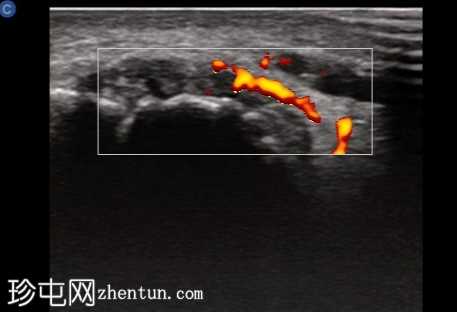

超声检查

纵轴切面

第一跖趾关节纵轴切面

关节积液伴轻度滑膜增生。高回声不规则沉积物,符合尿酸钠晶体沉积的典型表现。彩色多普勒成像显示滑膜充血活跃,符合急性炎症活动。